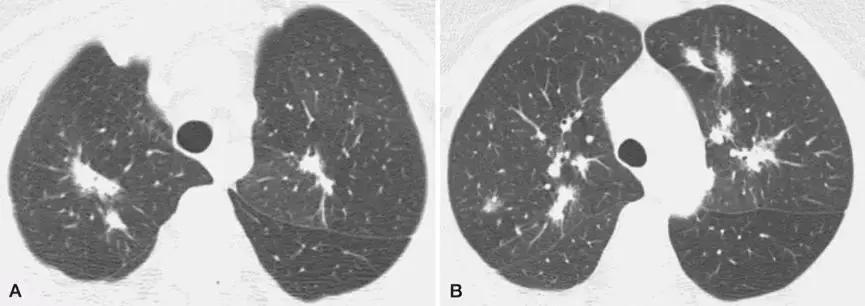

2、影像学是诊断线索

OP的影像表现:实变(周围、沿支气管血管束):80~95%;磨玻璃影:60~90%;小叶间隔增厚:55%;「反晕征」:20%;结节或团块:15~50%;还有「游走性」的特点。

结节或团块(需要和肿瘤鉴别):

孤立性肺炎型:则需要与结核、肺部肿瘤等进行鉴别。